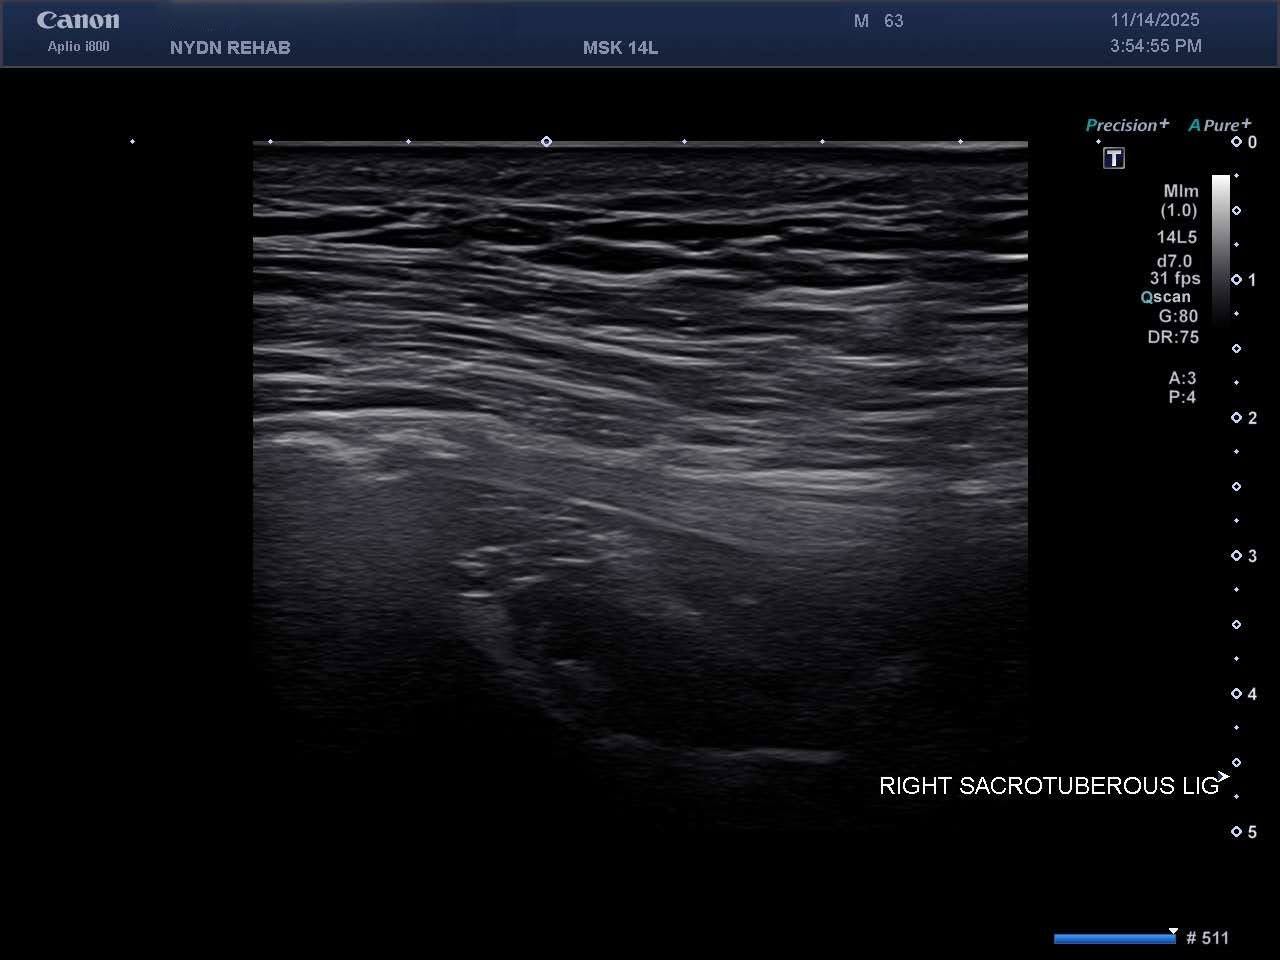

Ultrasound Images of SIJ Ligaments

• Sacrotuberous ligament thickening and enthesopathy